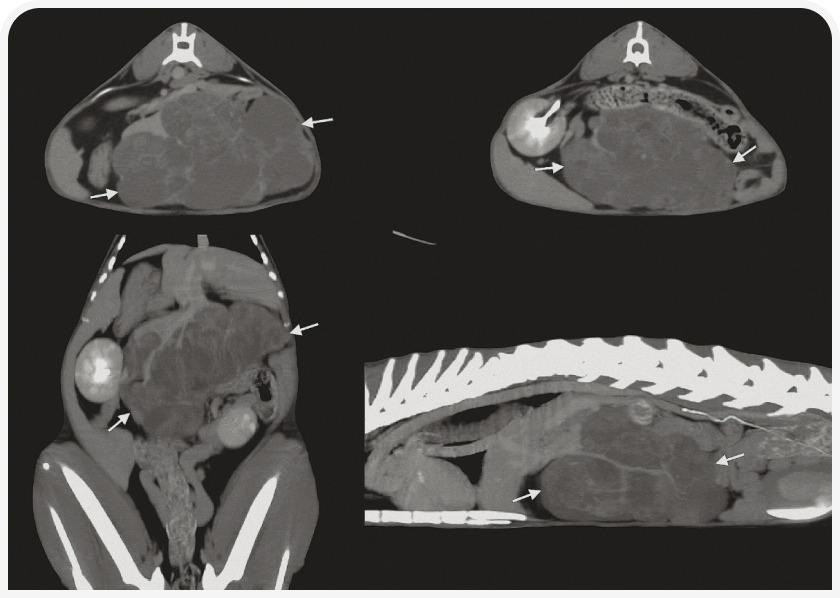

Для получения изображения методом КТ пациент должен находиться под общим наркозом, после чего ему внутривенно вводят йодированное контрастное вещество. Этот метод позволяет получить изображение печени целиком, особенно у крупных собак, у которых возможности ультразвукового исследования могут быть ограничены.

Собаку кладут на спину или на живот, а изображения, полученные в поперечной плоскости, переформатируют в другие плоскости.

В норме структура печени однородная, сигнал ослаблен в степени, типичной для мягких тканей. КТ особенно рекомендуется для оценки точного местоположения и возможной диссеминации образования в печени в случае, если планируется хирургическое вмешательство (Рисунок 5). Также очень полезно оценить аномалии строения сосудов, особенно портосистемные шунты (внутри- или внепеченочные); в этом случае требуется провести визуализацию после инъекций контрастного вещества в трех временных точках: во время артериальной, портальной и венозной фаз (2).